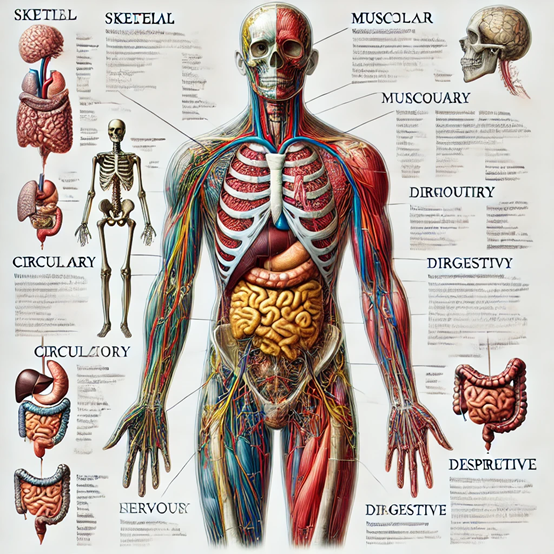

提示词:用一张图片介绍人体各个结构。

这个人体介绍图片就丰满很多,放在医疗介绍或PPT里应该不错吧。以后做各种宣传资料不愁找不到量身定制的图片了。

如果不满意,可以基于该图片继续发问,例如,我们想看上面人体介绍的骨骼。提示词:可以详细展示骨骼介绍吗?

我们放大手部骨骼,继续提问:来一张手部骨骼的特写。

需要注意的是,图像的文字介绍可能比较模糊或混乱,这是因为中文提示的原因,如果使用英文会好很多。